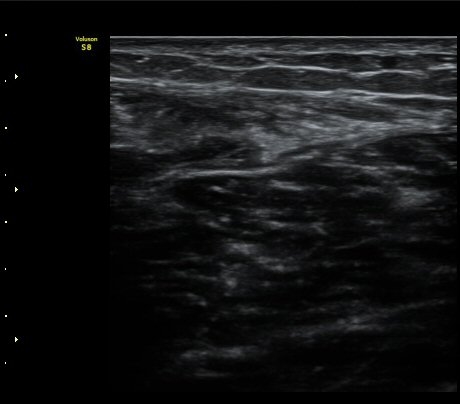

ºñº¹±Ù Ⱦ´Ü¸é°Ë»ç¿¡¼­ ºñº¹±Ù ³»Ãø, °¡Àڹٰ̱ú Á¢ÇÕ ºÎÀ§ÀÇ ÆÄ¿­°ú ¼ö¾× Àú·ù°¡ °üÂûµÊ(±×¸² 4)